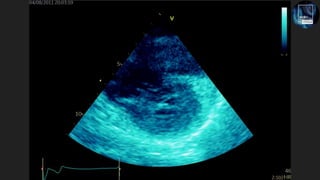

The document discusses the potential of echocardiography in managing cardiac arrest, emphasizing its non-invasive and painless nature for bedside assessments. It highlights the importance of recognizing the causes of cardiac arrest, such as hypovolaemia and tension pneumothorax, and the need for proper training of healthcare staff. Additionally, it provides resources for further learning, including social media and a dedicated website.